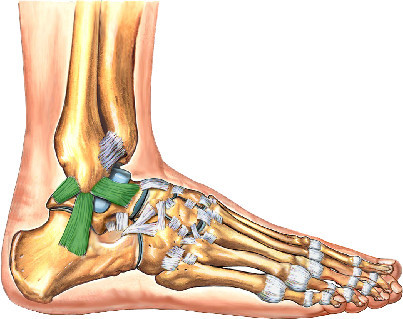

What is this structure?

Deltoid ligament of ankle

What is this structure?

Lateral ligament of the ankle